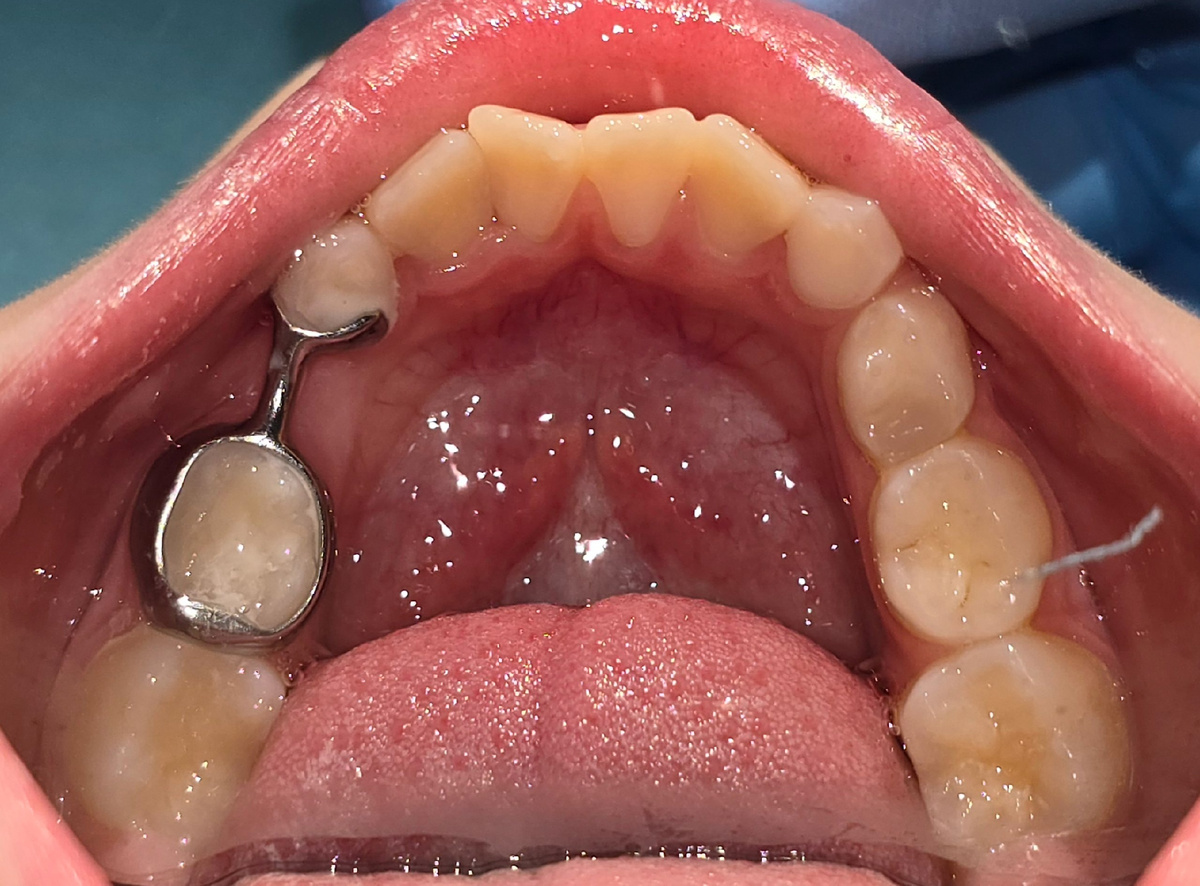

На второй фотографии представлено кольцо с распоркой. Его я рекомендую ставить, если отсутствует один зуб в одном сегменте.

В период ношения кольца и аппарата необходимо регулярно делать рентгенологический контроль, чтобы не пропустить момент прорезывания постоянного зуба.